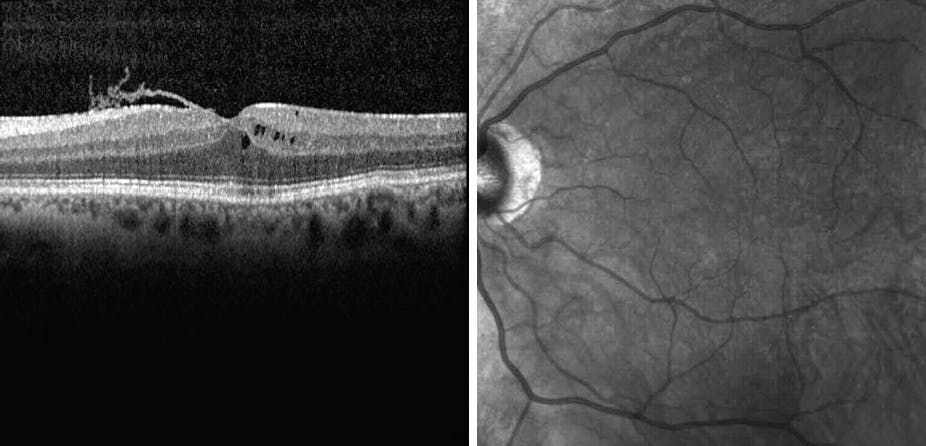

We recommended discontinuation of latanoprost. The patient saw a glaucoma specialist who substituted brimonidine 0.15% twice daily. One month later, his VA had improved to 20/20 OS with almost complete resolution of symptoms and CME on OCT (Figure 2).

<p>Figure 2. OCT 1 month after discontinuation of latanoprost shows resolution of CME.</p>

Figure 2. OCT 1 month after discontinuation of latanoprost shows resolution of CME.